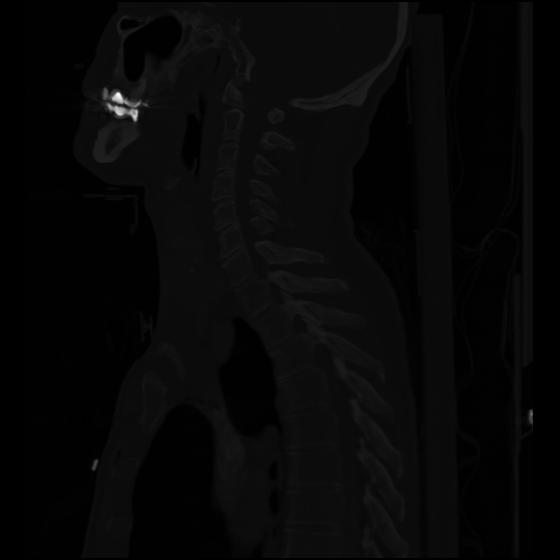

24 ANGIO,CE,Sag-MIP,5.000,ANGIO,Sag-MIP,